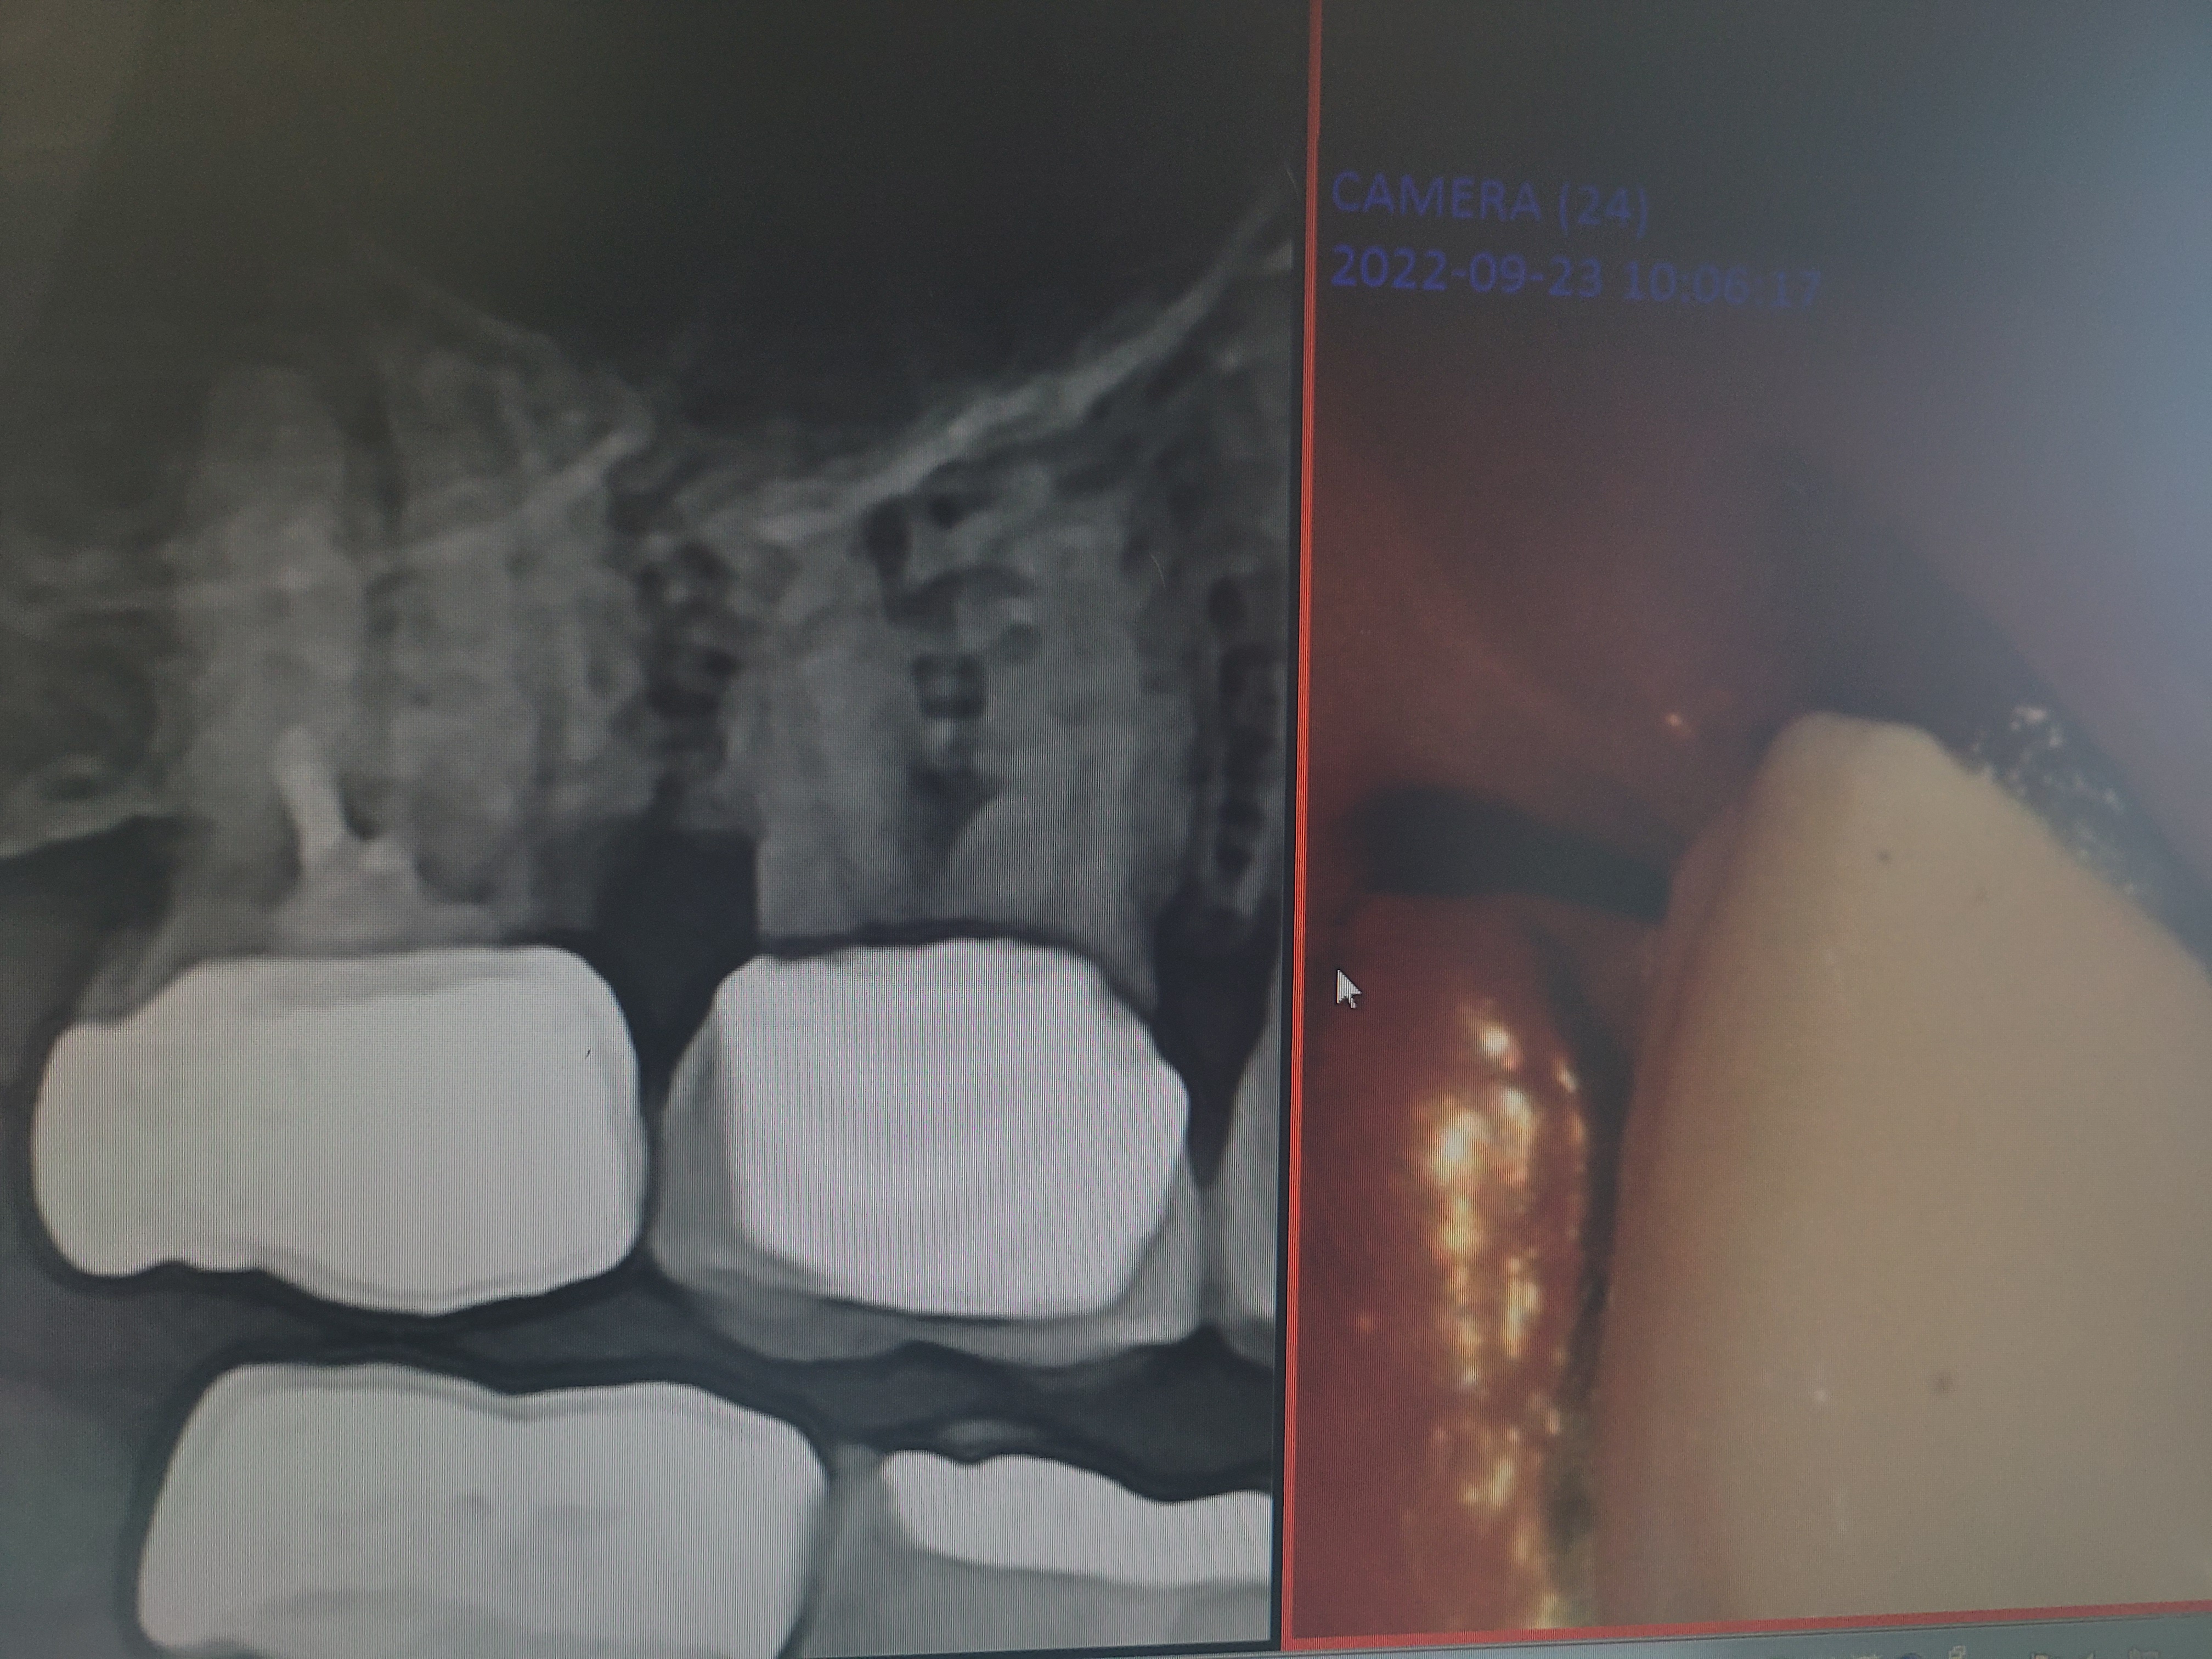

골드크라운, 지르코니아 크라운 및 임플란트 촬영 영상 사진

위의 10월 13일자 우측 사진이 좌측 아래 치아 상태입니다. 2021년 1월 12일자의 검은 어금니는 금니 크라운이 탈락한 상태입니다. 금니 크라운 아래에 썩은 충치가 가득하지만 신경치료가 되어 있어 별다른 불편은 없었습니다. 탈락을 했으니 교체하는 게 방법입니다. 그때도 금니 크라운을 지르코니아로 교체 하였습니다.

치과진료 치아 촬영 영상 사진이 작아서 잘 보이지 않을 수 있으나 10월 13일자 사진에 금니로 채운 부분(치아 보정 보철물) 다음에 있는 맨 뒤쪽 어금니가 지르코니아 크라운입니다. 아직 진료 시간이 얼마 되지 않았으며, 당연히 현재까지 전혀 불편함은 없습니다. 그렇다면 어차피 크라운 치료를 해야한다면 지르코니아와 골드 크라운 가운데 어느게 좋을까요?